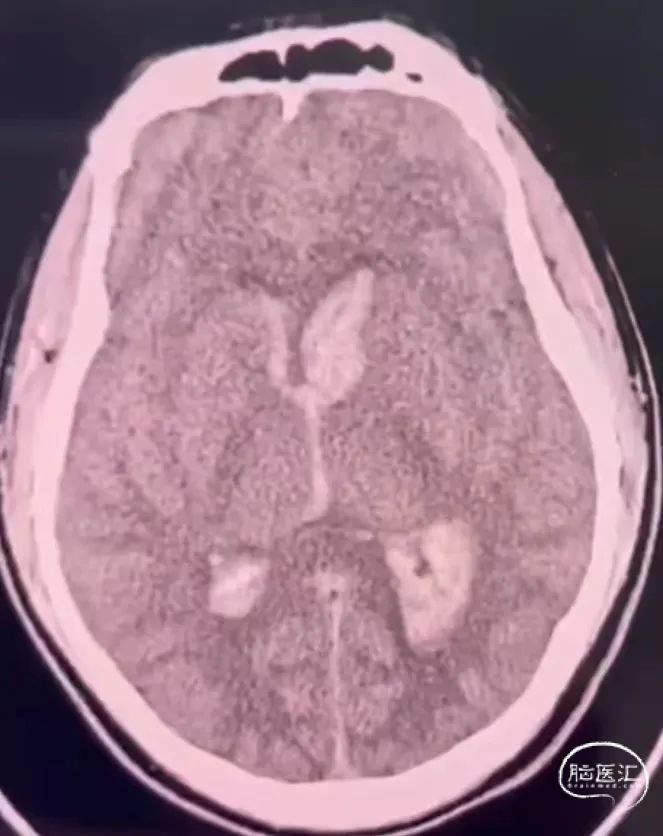

男,27岁,中度昏迷,AVM破裂出血破入脑室

双豆纹动脉加大脑中动脉分支供血,大脑大静脉引流,由于豆纹动脉与大脑中动脉成锐角,超选困难,采用球囊辅助echelon10才顺利进入豆纹动脉。

微导管自身block作用,无需做高压锅塞子,注胶过程几乎没有返流,Onyx胶很快完全弥散畸形团,闭塞引流静脉并倒灌其它供血动脉。

Onyx胶铸型完全,供血动脉、畸形团、引流静脉充分闭塞。术后正侧位及3D造影,畸形团及引流静脉完全不显影。